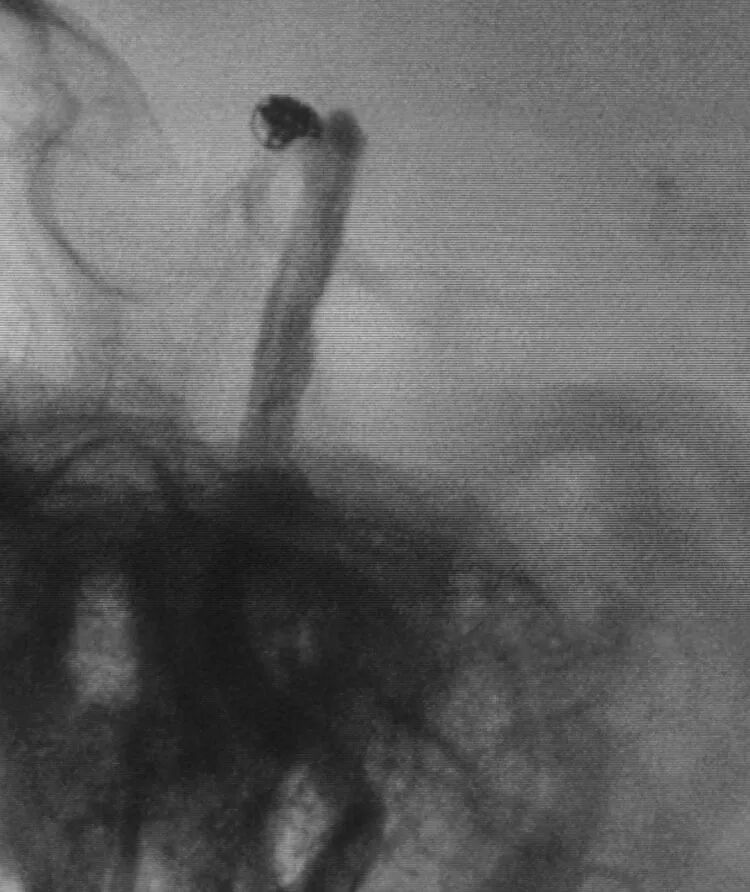

基底动脉顶端动脉瘤,瘤体长轴跟基底动脉主干平行

典型病例2